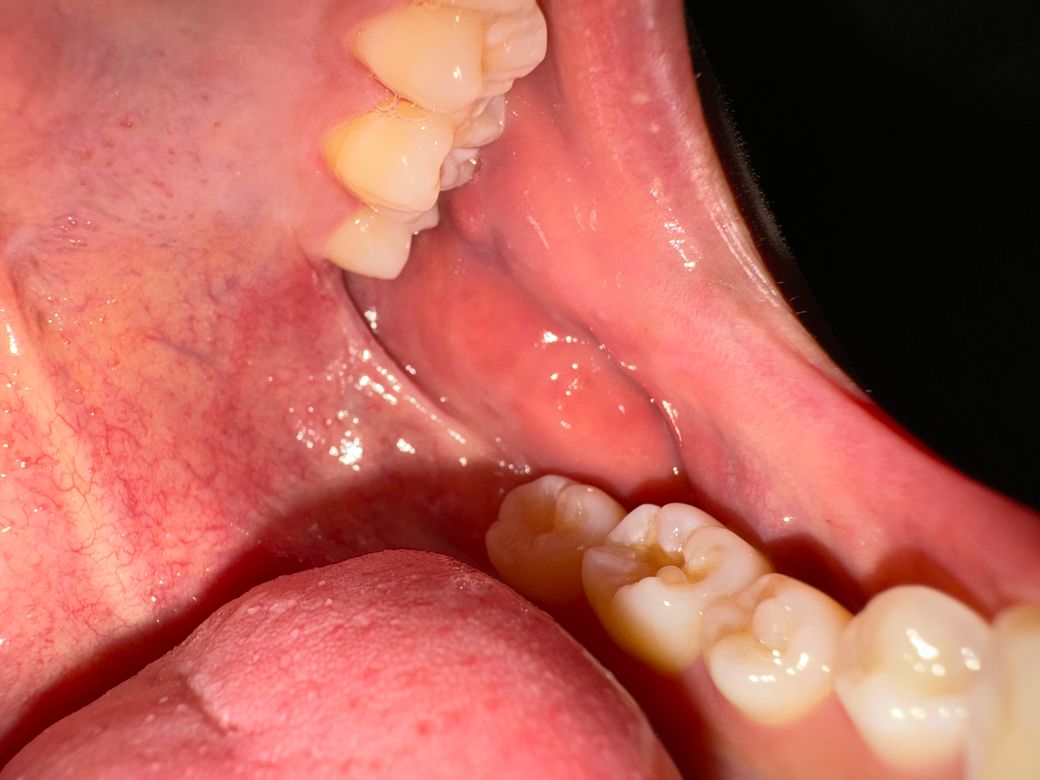

왼쪽 위 어금니 뒤 사랑니 나는 자리에 상처가 나있어요

5개월 전에 충치 땜빵할게 있어서 치과갔을 때 입을 크게 벌리면서 익돌하악봉선이 갑자기 엄청 땡기면서 그 부분이 찢어지고 상처가 났었는데 거기랑 이어지는 어금니 뒤쪽 사랑니 나는 자리에 흰색 뾰루지같은게 세개정도 나있어요. 크게 아프진 않고 신경 쓰일 정도로 쓰라린 정도인데 뭘까요? 한 3일정도 됐고 익돌 하악봉선쪽에 찢어진건 5개월 됐습니다. 두달정도 전에 치과갔을 때는 구강암같은건 아니라고하시고 연고 주셔서 며칠 바르니까 완치는 아니고 거의 나았었는데 이게 또 재발한걸까요? 사진상으로 심각한 병으로 보이시나요? (참고로 저 부위에는 사랑니가 없습니다.)

• 1번 째 사진

사진상 봤을때는 특별히 악성 병소의 양상은 아니나 정확한 검사를 위해서는 대학병원의 구강내과에서 조직검사를 해보면 좋을 것 같습니다.